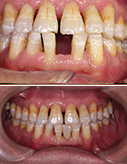

侧切牙太小不美观,瓷贴面完美解决

“查漏补缺”,瓷贴面也在行